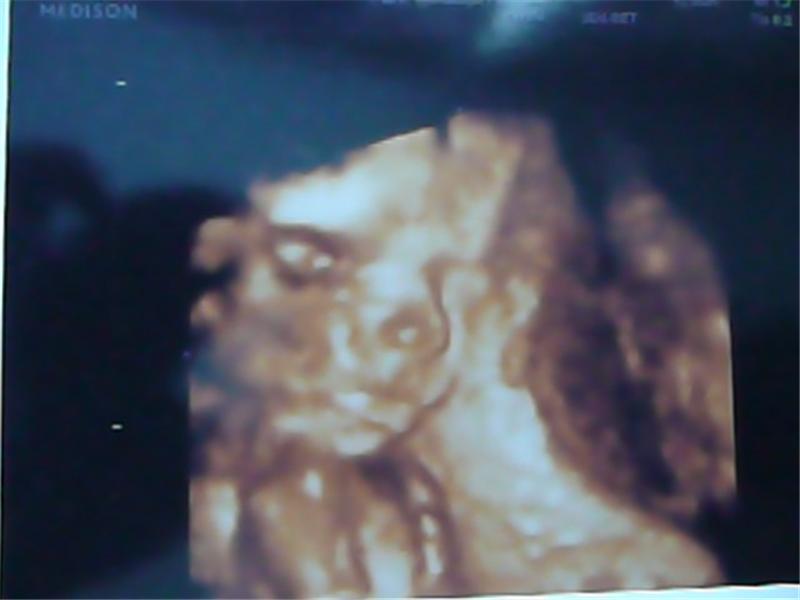

Justýnka 6.11.2010